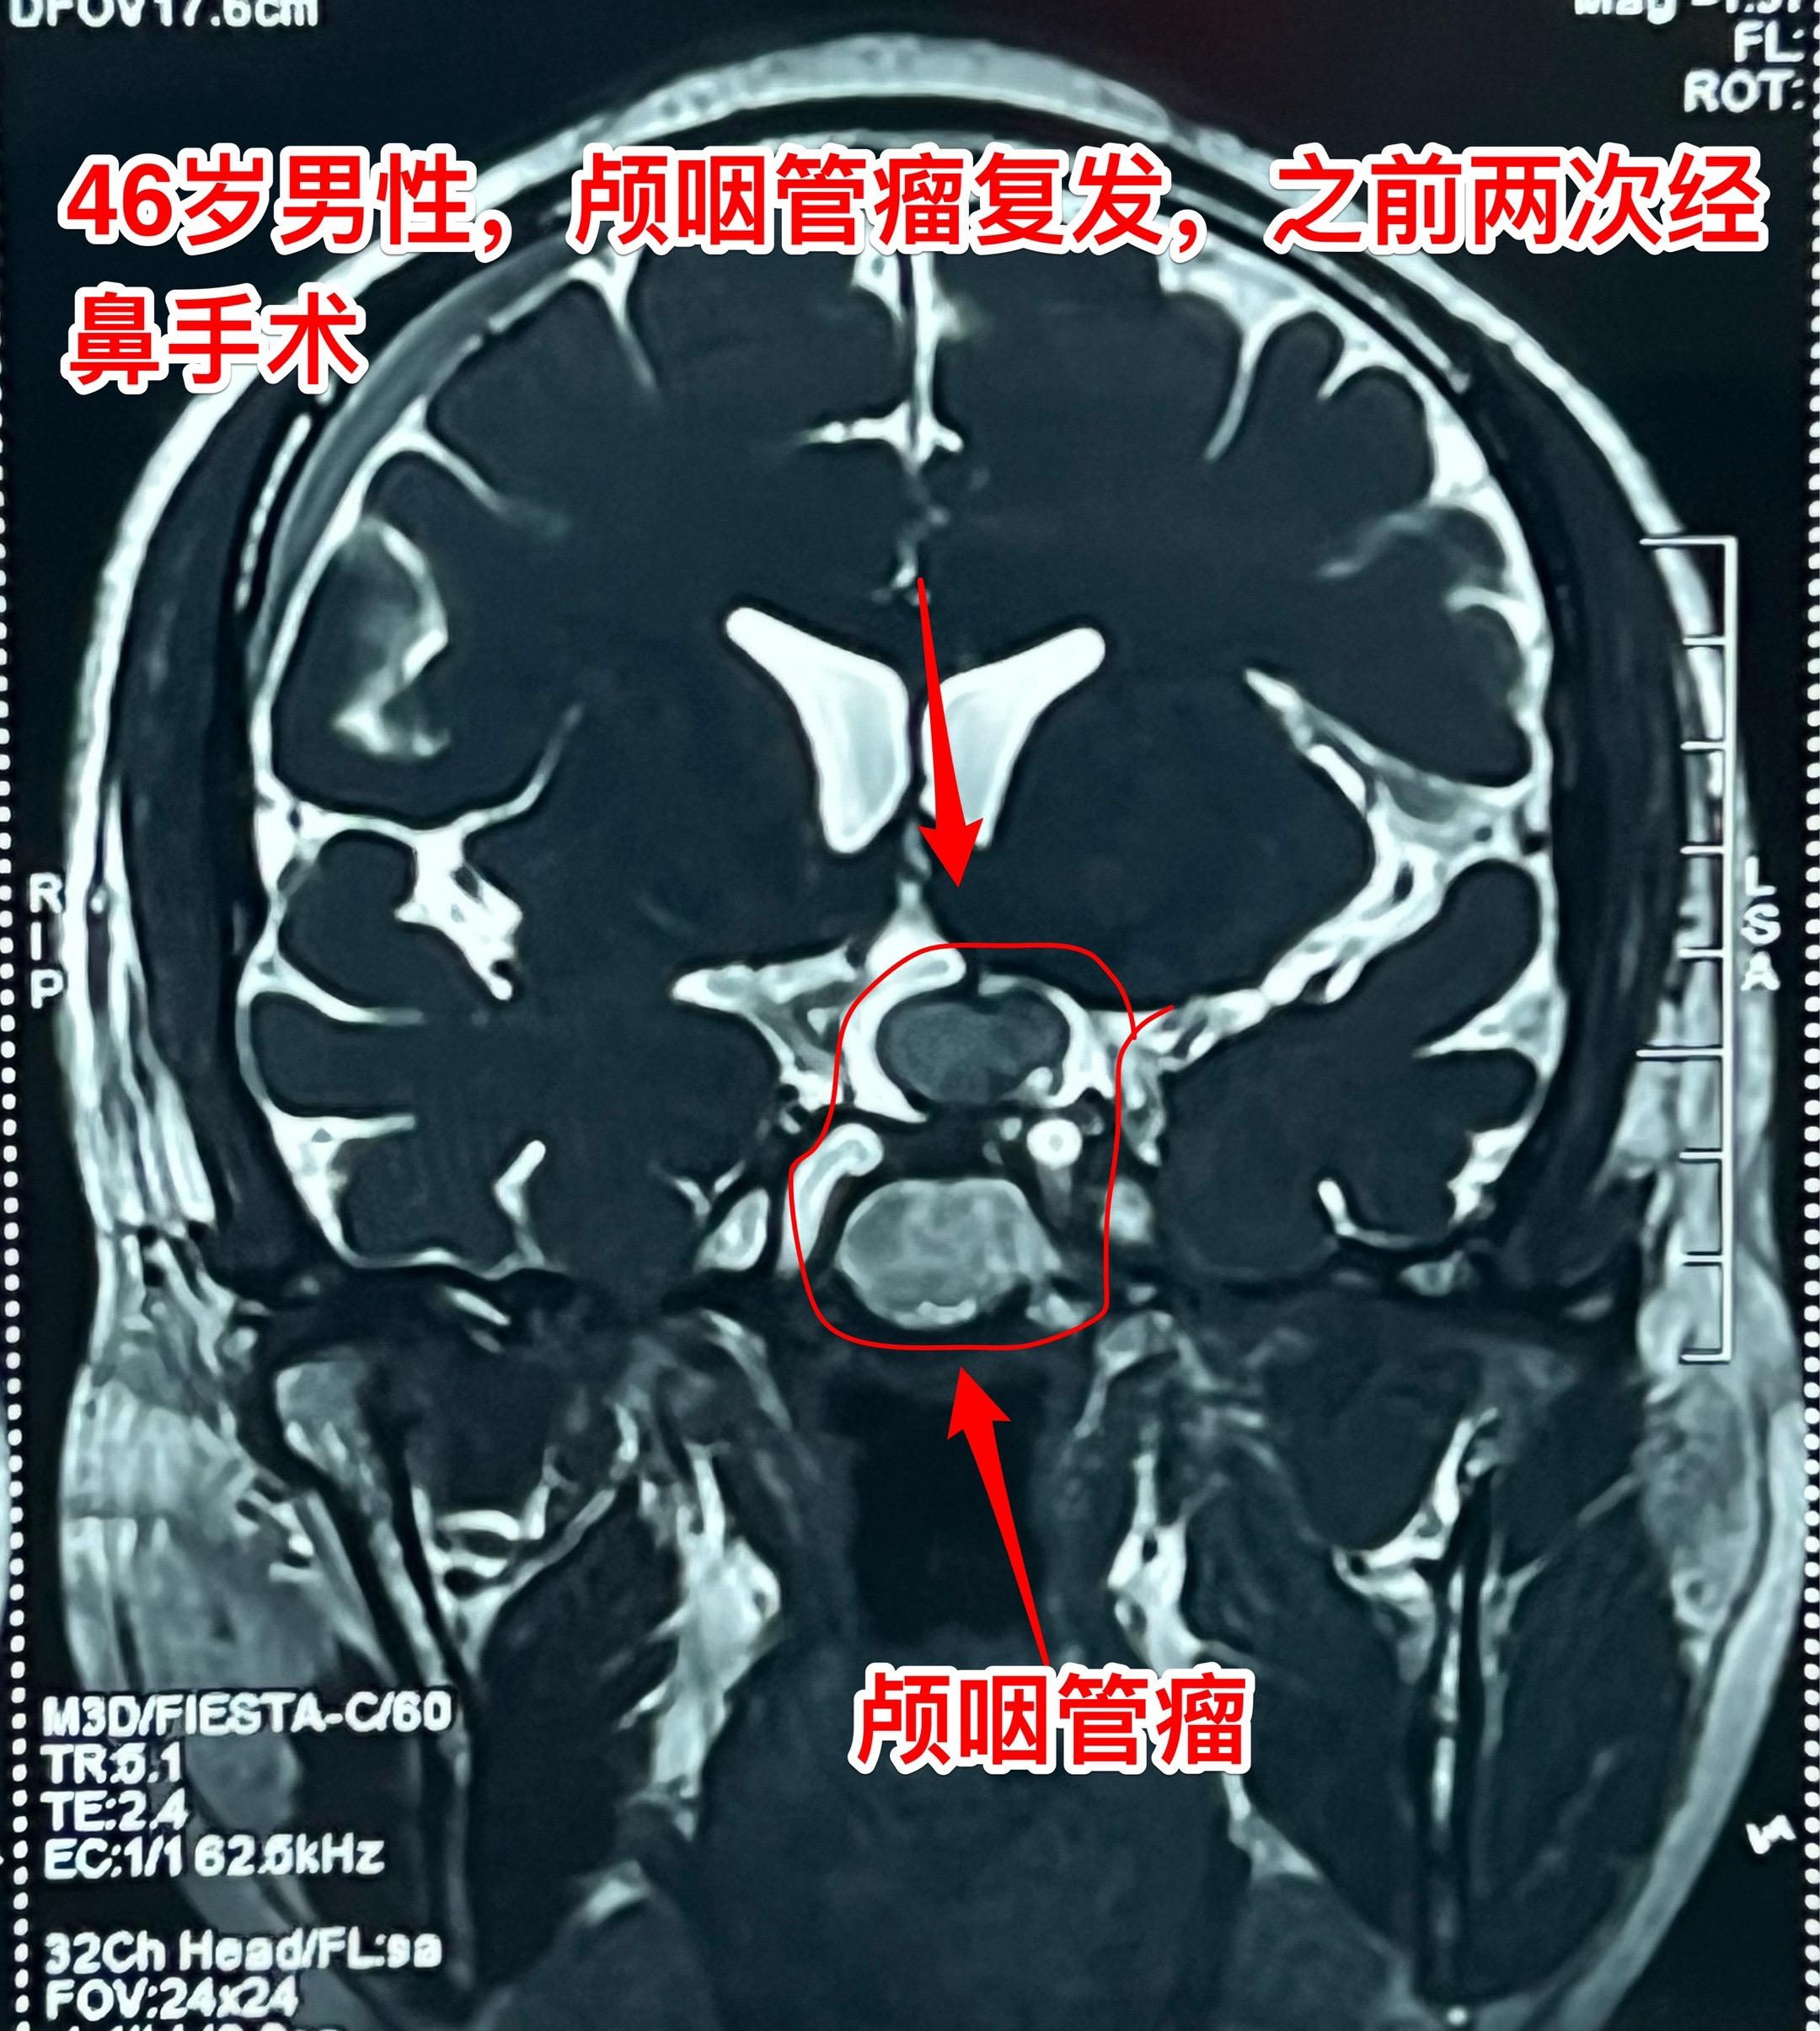

2024年12月2日视频中男主现在上班了。该宜宾市男子因两次经鼻手术切除颅咽管瘤后出现左眼失明,右眼视力几乎失明,于2024年11月26日在我科作了开颅手术,术后视力恢复。 2025年3月12日患者的妻子告诉我患者已经上班了,左眼视力恢复到0.25,右眼视力0.1,记忆力好转,并发了上班的视频。视频截屏及对话截屏见照片。 希望颅咽管瘤不再复发!